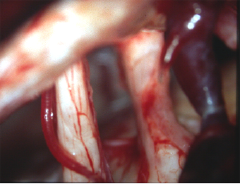

小脳橋角部の典型的な類表皮のう胞 epidermoid cyst

60代の女性の手術中の写真です。この女性も三叉神経痛で発症した小脳橋角部の類表皮のう胞です。左の写真で,白く光って真珠のように見えるの (pearly tumor) が腫瘍です。右側は腫瘍を全部とり終えた後の写真です。三叉神経の真ん中が凹んでいました。この患者さんも症状は消えて再発はしていません。でも,三叉神経痛で発症した患者さんの治療は必ずしも容易ではありません。